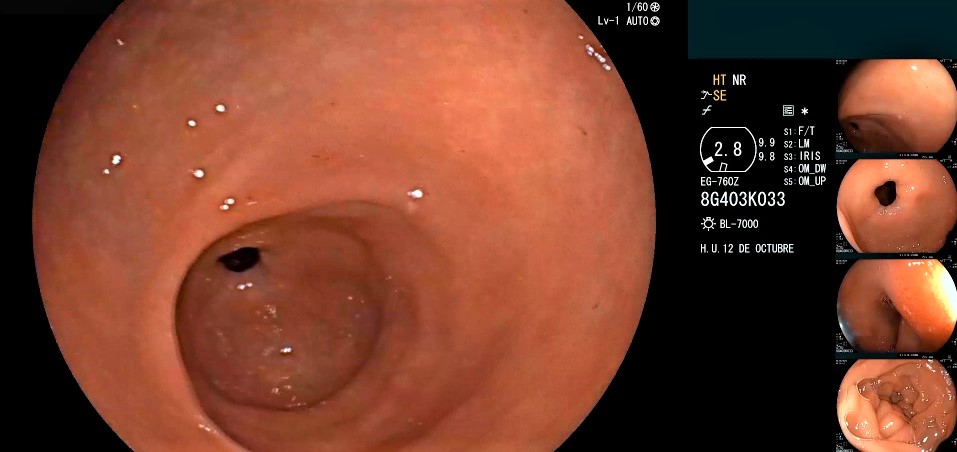

Una vez que hemos pasado la zona de la incisura, ya en el antro, lo primero que nos vamos a encontrar de frente y en el centro, si no existe anomalía anatómica, será el orificio del píloro, el canal pilórico, desde donde se ve y accede a la primera parte del duodeno, el bulbo duodenal.

El duodeno es la primera porción del intestino delgado y comienza justo después del estómago, en el píloro.

Anatómicamente, tiene una forma de “C”. En la endoscopia alta se revisa la primera porción o bulbo, la segunda porción y nos asomamos a la tercera. El gastroscopio logra, como mucho, analizar esta tercera porcion duodenal.

Al visualizar el bulbo duodenal se observa una cavidad amplia, cubierta por una mucosa lisa, sin pliegues marcados. Esta región se conecta directamente con el píloro, la válvula que regula el paso del contenido gástrico al intestino delgado.